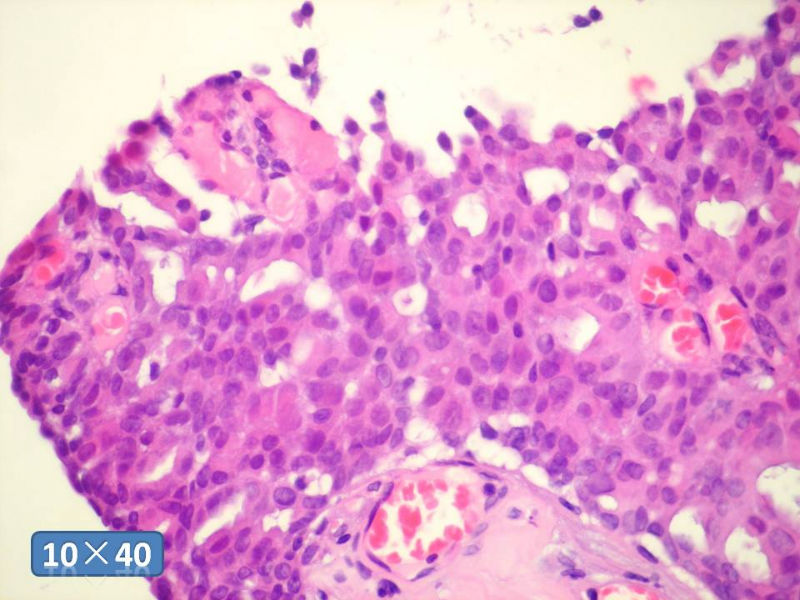

只能说是乳头状瘤

是不是导管内

乳头状瘤 and 导管内乳头状瘤 are the same; Benign lesion.

After you work up and you still cannot be sure it is benign , atypical or maignant lesion, you can call 乳头状lesion.

If this is excisonal case, you should figure out the nature of the papillary lesion.

我的意思就是提醒大家 在不是很确定的情况下 尽量少给自己套枷锁